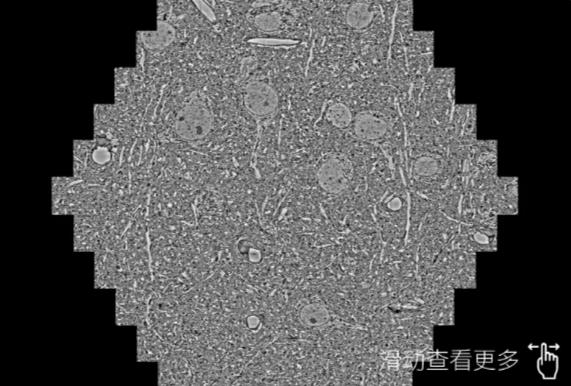

鼠脑切片。左图使用葫芦岛蔡司葫芦岛扫描电镜MultiSEM706对165μmx143pm面积区域成像,耗时仅需1.5秒。右图为鼠脑切片中30μm区域放大效果。样品由芝加哥大学B.Kasthuri提供。